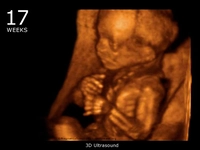

23 haftalık gebelik, hamileliğin ikinci trimesterinin sonlarına yaklaşıldığı bir dönemi ifade eder. Bu süre zarfında, hem anne hem de bebek için birçok önemli gelişim ve değişiklik yaşanmaktadır. Bu makalede, 23 haftalık gebelik dönemindeki fiziksel ve duygusal değişimlerin yanı sıra, bebeğin gelişimi, anne adayının sağlığı ve dikkat edilmesi gereken hususlar ele alınacaktır. Bebeğin Gelişimi23 haftalık gebelikte bebek, hızla büyümeye devam etmekte ve birçok önemli gelişim sürecinden geçmektedir. Bu dönemde, bebeğin gelişimiyle ilgili bazı önemli noktalar şunlardır: